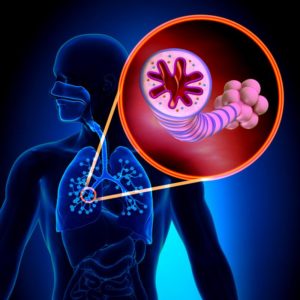

La pillola per l’asma prende di mira i muscoli delle vie aeree per diminuire gli attacchi

Immagine, ostruzione del lume di un bronchiolo da parte dell’essudato mucoso, metaplasia delle cellule caliciformi e ispessimento della membrana basale…